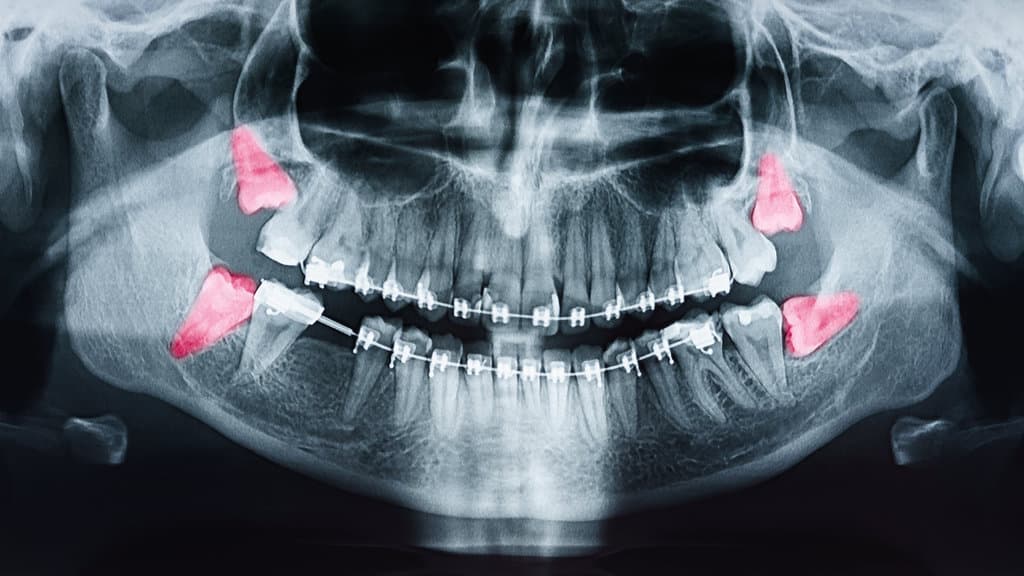

As individuals reach late adolescence and early adulthood, the emergence of third molars often presents a variety of clinical challenges, necessitating careful evaluation by dental professionals. Impacted teeth, a common issue with wisdom teeth, occur when these molars fail to erupt properly due to spatial constraints or malalignment. This condition can lead to pericoronitis, characterized by inflammation and infection of the surrounding soft tissue. Additionally, impacted wisdom teeth are frequently associated with the formation of dental cysts, specifically dentigerous cysts, which can cause resorption of adjacent tooth roots and weaken the jaw structure. Early detection through radiographic imaging and clinical assessment is critical to managing these complications effectively. Such evaluations assist in preventing further oral health deterioration and guide appropriate intervention strategies.

When individuals suspect that their wisdom teeth may be influencing their blood pressure, it is imperative to employ a systematic approach grounded in clinical evidence. Initially, it is advisable to consult with a dental professional to evaluate the status of the wisdom teeth through radiographic imaging. This assessment will determine if impaction or infection is present, which could potentially contribute to systemic conditions such as elevated blood pressure. Concurrently, monitoring blood pressure levels using a calibrated sphygmomanometer provides objective data to establish any correlation between dental health and hypertension. Should a causal relationship be identified, interdisciplinary management involving both dental and medical practitioners becomes essential. Treatment may include the extraction of problematic wisdom teeth or pharmacological intervention to mitigate hypertensive symptoms.